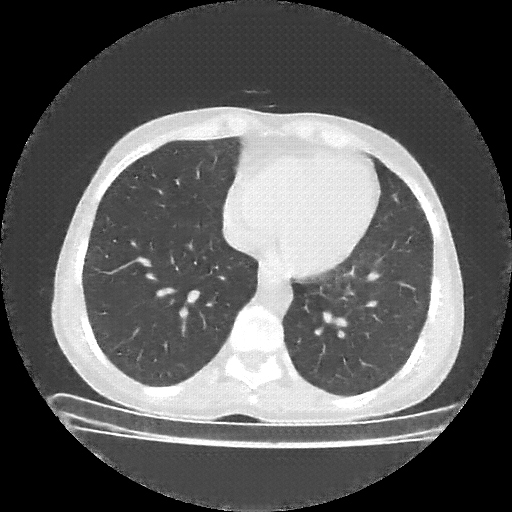

Original NATIVE CT scan (input)

No window - Raw intensity values

Lung window (WL -600, WW 1500 β†’ Low βˆ’1350, High +150)

Mediastinum window (WL 40, WW 400 β†’ Low βˆ’160, High +240)

Targeted Slice 70 - Lung Window Analysis (Generated vs Real Venous)

0.735

Lung SSIM

98.3

Lung RMSE

42.7

Lung MAE

Average Lung Window Metrics Across All Slices (38 slices) - Generated vs Real Venous

0.745

Lung SSIM (Avg)

101.6

Lung RMSE (Avg)

42.0

Lung MAE (Avg)